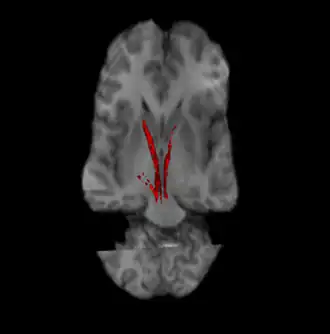

Nigrostriatal pathway (Left and Right in red).